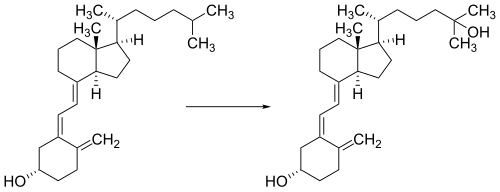

Whether synthesized in the skin or ingested, vitamin D is hydroxylated in the liver at position 25 (upper right of the molecule) to form the prohormone calcifediol, also referred to as 25(OH)D).[3] This reaction is catalyzed by the microsomal enzyme vitamin D 25-hydroxylase, the product of the CYP2R1 human gene.[203] Once made, the product is released into the blood where it is bound to vitamin D-binding protein.[204]

Calcifediol is transported to the proximal tubules of the kidneys, where it is hydroxylated at the 1-α position (lower right of the molecule) to form calcitriol (1,25-dihydroxycholecalciferol, also referred to as 1,25(OH)2D).[1] The conversion of calcifediol to calcitriol is catalyzed by the enzyme 25-hydroxyvitamin D3 1-alpha-hydroxylase, which is the product of the CYP27B1 human gene. The activity of CYP27B1 is increased by parathyroid hormone and also by low plasma calcium or phosphate.[1] Following the final converting step in the kidney, calcitriol is released into the circulation. By binding to vitamin D-binding protein, calcitriol is transported throughout the body.[14] In addition to the kidneys, calcitriol is also synthesized by certain other cells, including monocyte-macrophages in the immune system. When synthesized by monocyte-macrophages, calcitriol acts locally as a cytokine, modulating body defenses against microbial invaders by stimulating the innate immune system.[205]